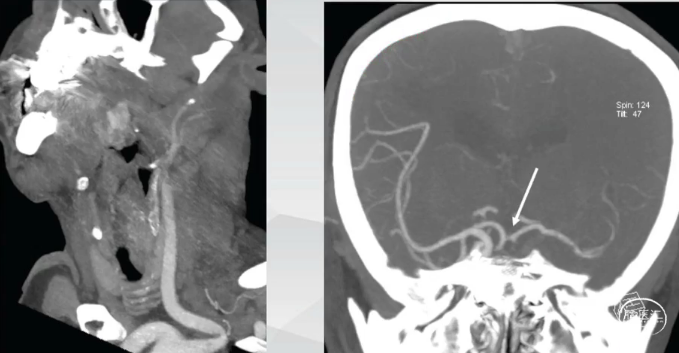

CTA:左侧颈内动脉-大脑中动脉串联闭塞,前交通开放右向左代偿供血。